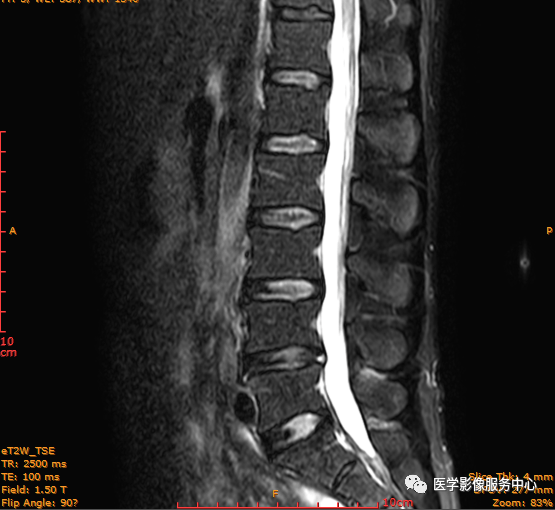

临床诊断 :腰突症?故行腰椎MRI检查,图像如下:

矢状位PD压脂序列

T2矢状位

T1矢状位

这个患者腰椎间盘膨出程度不明显,神经根没有明显的受压,椎管未见明显狭窄,那这个患者腰疼的“罪魁祸首”是腰椎间盘膨出嘛?

L3-4椎间盘后缘可见点状高信号区(红色箭头所指处)

红色箭头所指的异常信号区是是什么呢?平时工作中大家有没有遇到这种情况,你会不会忽略这个异常信号?有没有想过这个椎间盘后缘高信号区是引起患者腰疼的重要因素呢?下面为大家重点介绍。

腰椎椎间盘高信号区是诊断椎间盘源性腰痛的重要MRI征象,且在急性重度下腰痛患者中更明显。HIZ 由 Aprill 和 Bogduk 在1992年首次描述,即 矢状位MRI T2加权像显示腰椎间盘后缘小而圆或线状的局限性高信号区。

影像表现主要在T2矢状位及T2横断位可见椎间盘前缘或后缘可见高信号区;

L3-4椎间盘后缘HIZ

日常工作因腰腿疼痛来检查腰椎MRI的很多,而腰腿疼痛并不一定就是腰椎椎间盘突出或膨出导致的,我们应该需要知道椎间盘HIZ也会引起腰腿疼痛,这种椎间盘源性的疼痛我们不能“忽略”;椎间盘后方HIZ并不少见,椎间盘后方 HIZ 在 T2WI 的局限性高信号、T1WI 呈局限性较低或等信号意味着通常所指的纤维环破裂伴随肉芽组织长入;而 T1WI、T2WI 均呈高信号可能是钙化组织。